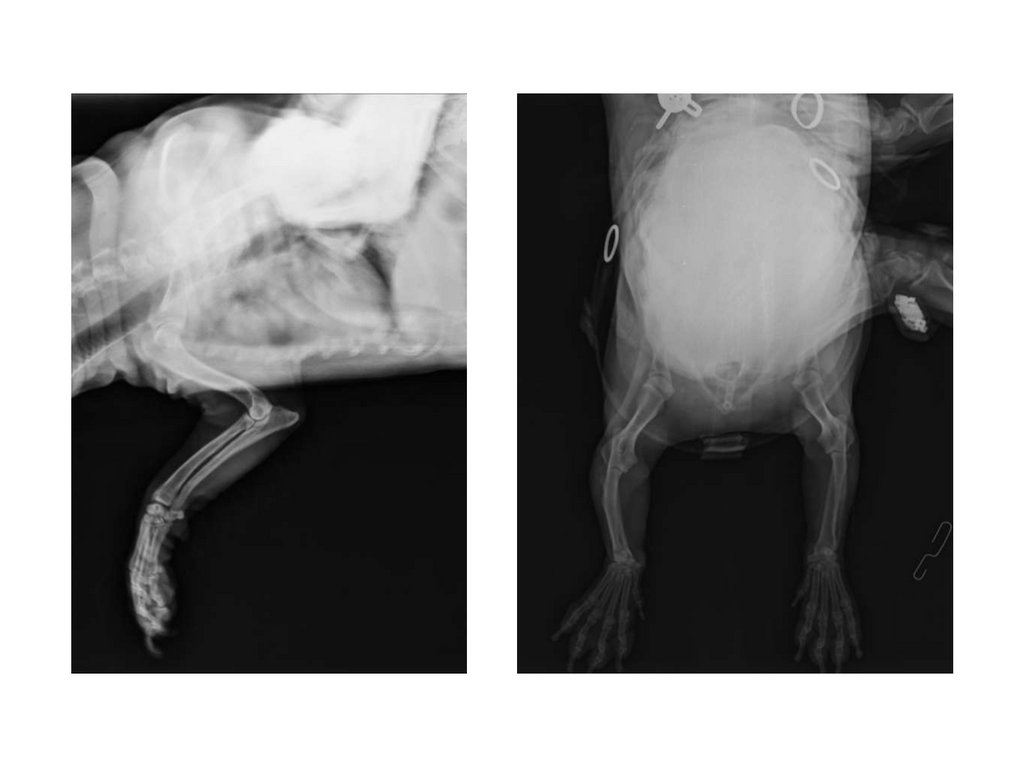

Вест-хайленд-уайт терьер

Кобель, 7 лет

- хромота на правую грудную конечность в течение 4 недель

- со слов владельцев усиливается

- при ортопедическом и неврологическом осмотре без признаков патологии

Данные визуальной диагностики:

- на предоставленных владельцами рентген-снимках признаков патологии не определяется